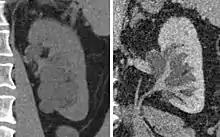

Advanced polycystic kidney disease with multiple cysts.[12]